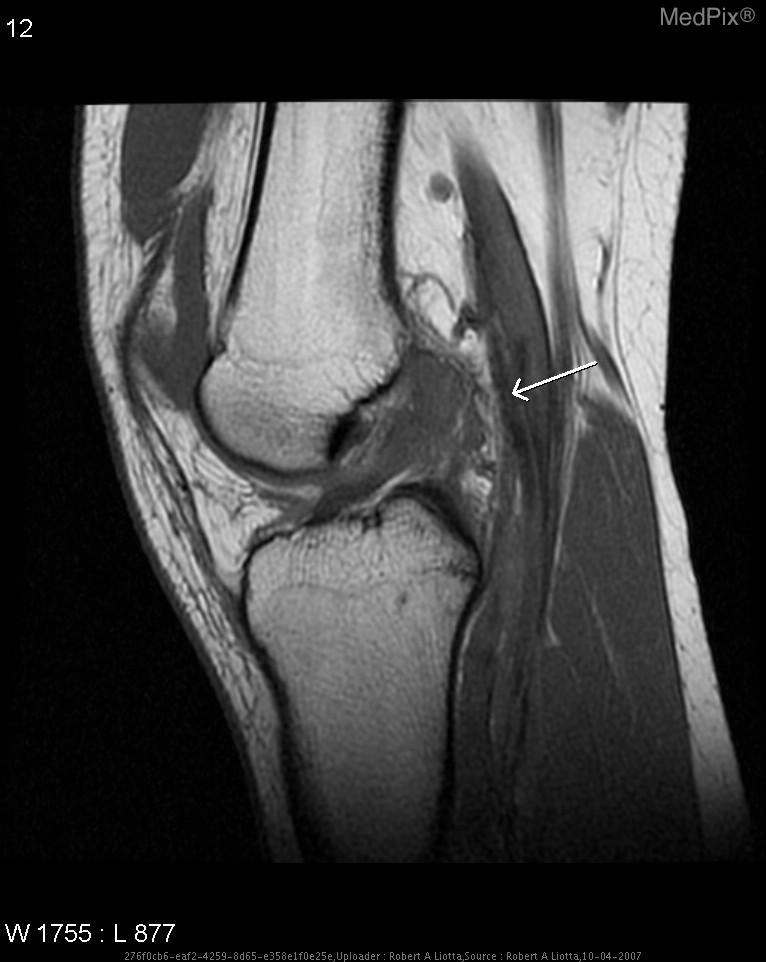

Meniscal Tear

The meniscus is cartilage in the knee that acts as a shock absorber as well as helping control the motion of knee bending, straightening, and twisting. Often this tissue tears with excessive load in a weightbearing position with a knee twist. While a tear in the meniscus is often excised or repaired surgically, often people can rehabilitate through this injury without surgery. At Goodell Physical Therapy, we can help diagnose a torn meniscus and provide guidance in safe, proper rehabilitation technique, as well as recommend a good orthopedic surgeon if necessary.

The ACL is extremely important for the stability of the knee joint. It is often sprained or torn in a knee hyperextension injury, and often also involves a tear of the meniscus as well. Not only can we, at Goodell Physical Therapy, help diagnose and rehabilitate an ACL tear pre and post-surgery, but we can also help patients prevent ACL tears through education in proper movement patterns and stability exercises in both the athlete and the general population.